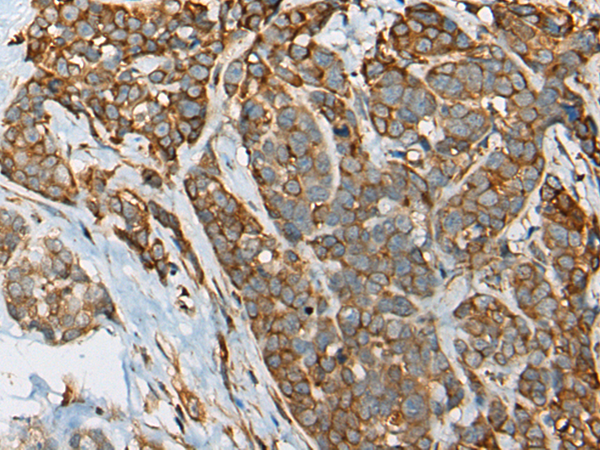

分类: 科研抗体货号: P12859别名: YB1; BP-8; CSDB; DBPB; YB-1; CBF-A; CSDA2; EFI-A; NSEP1; NSEP-1; MDR-NF1应用: IHC反应种属: Human, Mouse, Rat